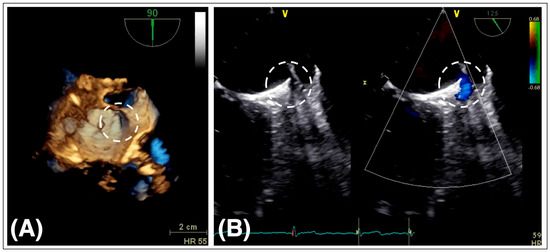

6.1. Device-Related Thrombosis

6.2. Peri-Device Leaks